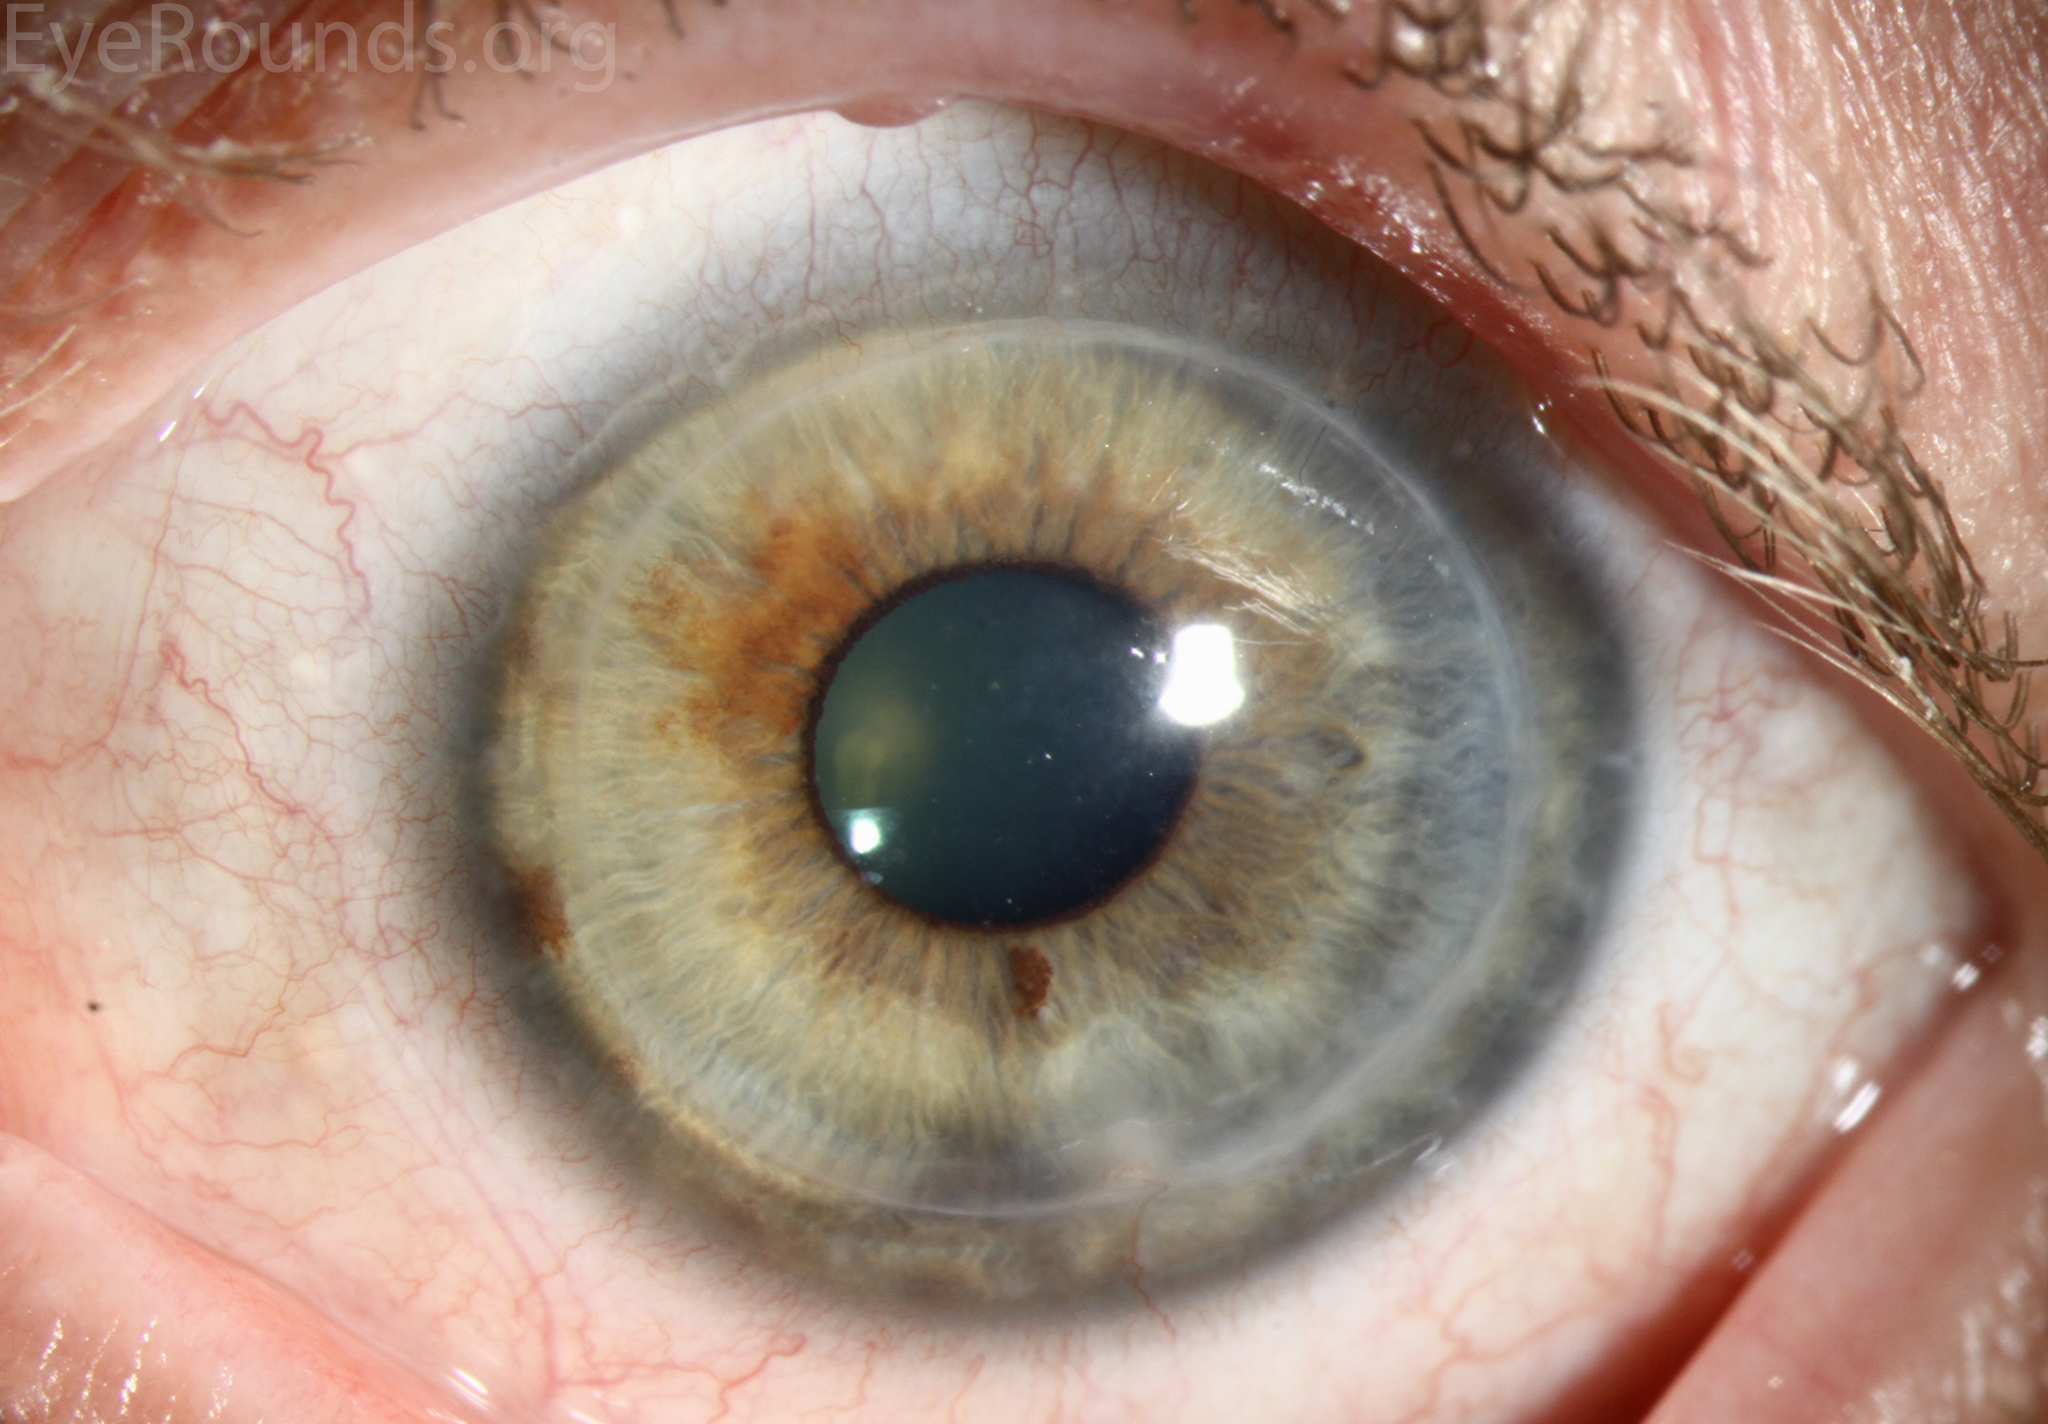

PK is a full-thickness transplant procedure, in which a trephine of an appropriate diameter is used to make a full-thickness resection of the patient's cornea, followed by placement of a full-thickness donor corneal graft. Interrupted and/or running sutures are placed in radial fashion at equal tension to minimize post-operative astigmatism (Figure 2). Later, the sutures are removed selectively to reduce the amount of astigmatism present. A transplant can last decades with proper care (Figure 3). While once the most prominent type of corneal transplant, PK has been supplanted by partial thickness techniques for endothelial dysfunction without significant stromal scarring. PKs are performed primarily for visually significant stromal scarring, opacities with an uncertain status of the endothelium or significant posterior corneal involvement, corneal ectasia (such as keratoconus and pellucid marginal degeneration, especially if there is history of hydrops), combined stromal and epithelial disease (such as Peters anomaly), and infectious or non-infectious corneal ulcerations or perforations (1, 14). A variant of the procedure, the mini-PK, can be used to treat more focal defects in the cornea (Figure 4).